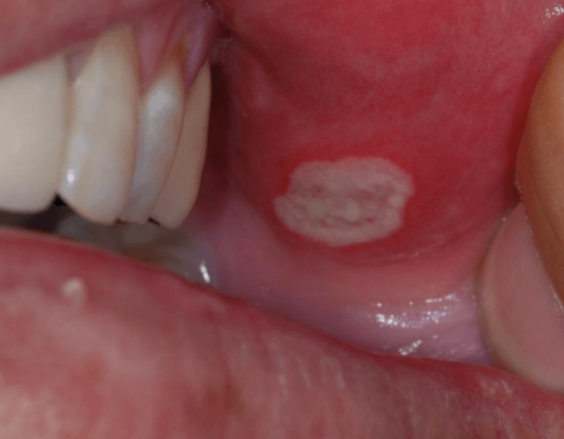

구내염은 입안 점막에 생기는 염증성 질환으로,

작게는 2~3mm부터 크게는 1cm 이상의 궤양(white ulcer)이 발생할 수 있습니다.

● 1. 하얀색 또는 노란색의 궤양

구내염의 가장 대표적인 형태입니다.

작은 점처럼 보이기도 하고 원형의 얕은 상처처럼 보이기도 합니다.

● 3. 붉게 부어오름

궤양 주변이 붉게 충혈되고 살짝 부어오르는 경우가 많습니다.